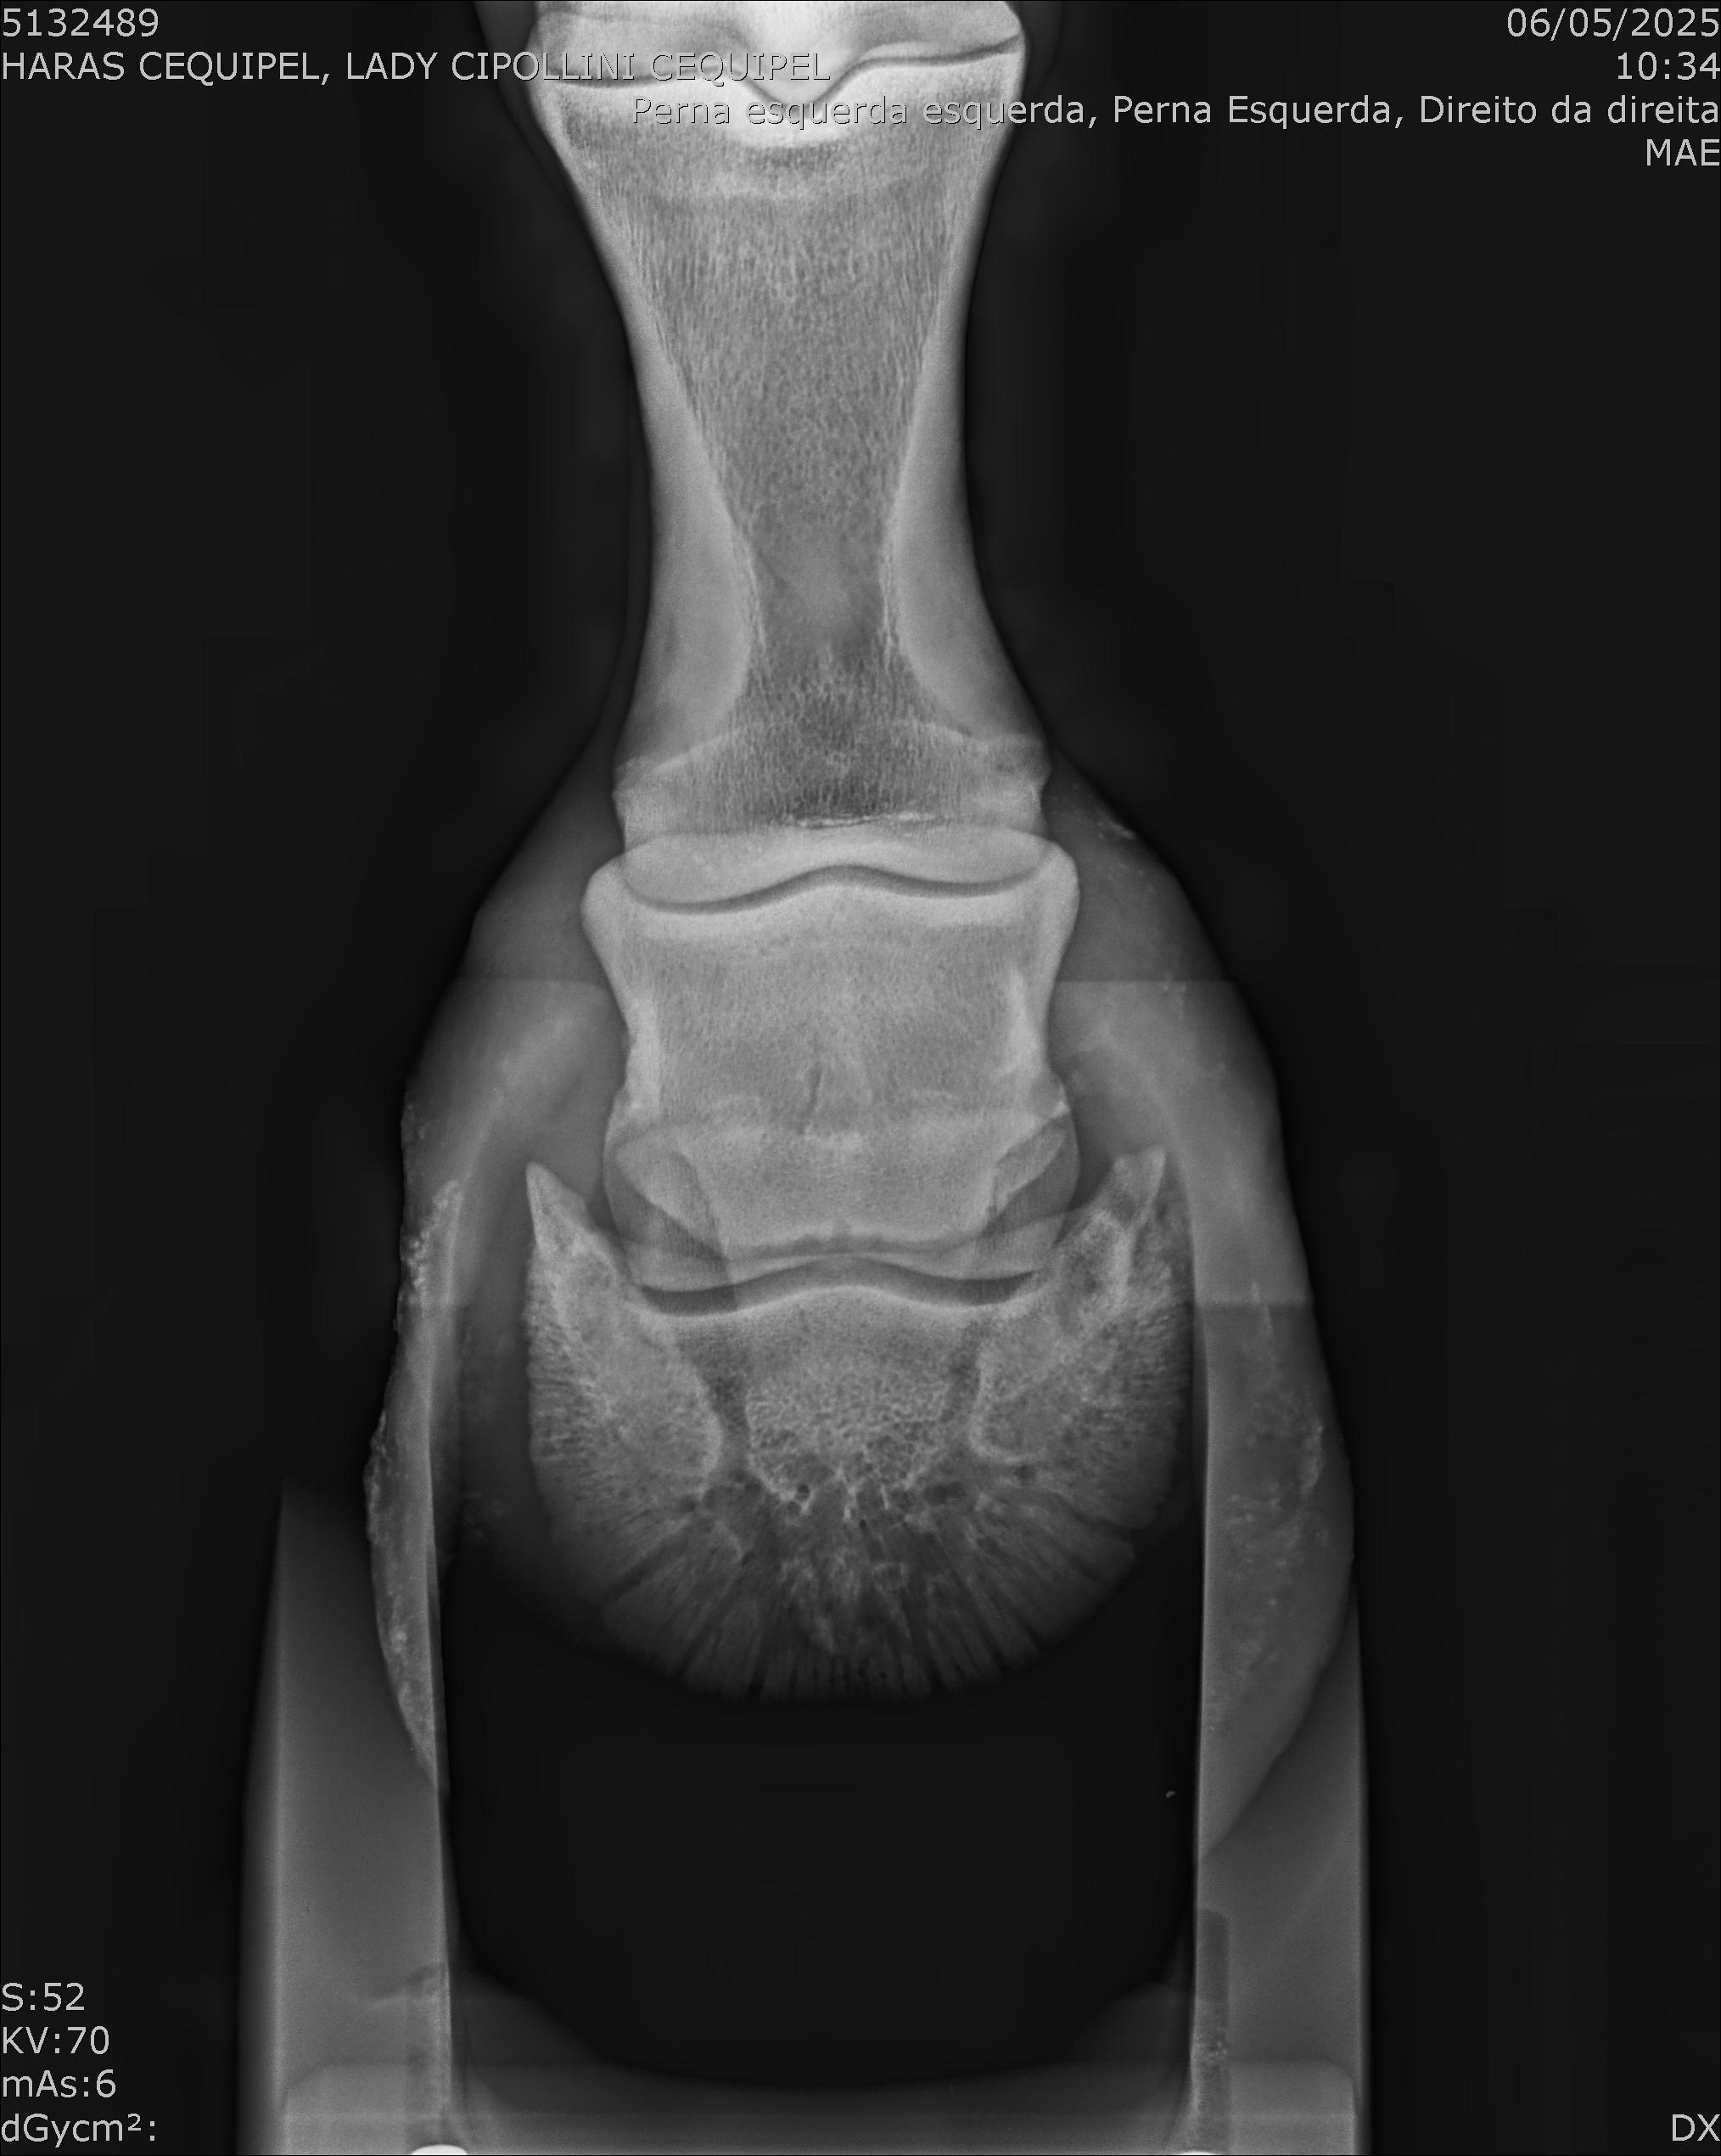

:: RAIOS-X DO LOTE